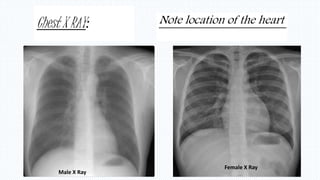

HEART POSITION IN THE THORAX

From 2nd rib – 5th I/C space

Apex – 1 cm inside to left mid clavicular line

Chest X RAY:

Male X Ray

Female X Ray

Note location of the heart